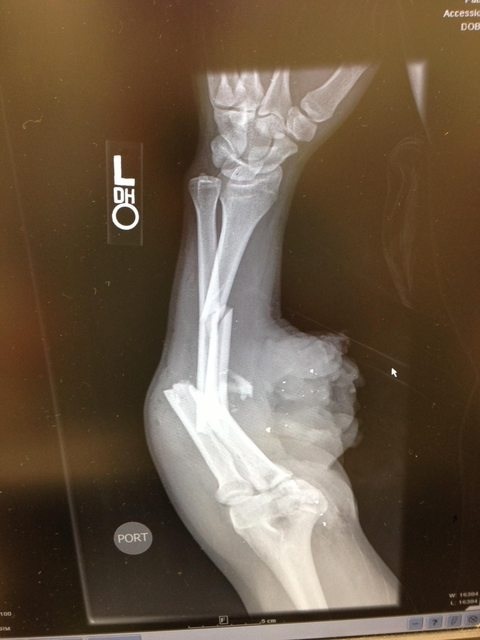

Arm shot with an AK-47...

jimf67L.jpg